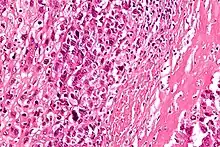

Au microscope la caractéristique de l'ostéosarcome est la présence d'ostéoïde (formation osseuse) dans la tumeur. Les cellules tumorales sont très pléomorphes (anaplasiques), certaines sont géantes, et de nombreuses mitoses sont atypiques. Ces cellules produisent des ostéoïdes décrivant des travées irrégulières (amorphes, éosinophiles / roses) avec ou sans calcification centrale (hematoxylinophilic / bleu, granulaire) - os de la tumeur. Les cellules tumorales sont incluses dans la matrice ostéoïde. Les ostéosarcomes peuvent présenter des cellules géantes ostéoclastiques comme multinucléées[7].

Selon les caractéristiques des cellules tumorales présentes (qu'elles ressemblent à des cellules osseuses, à des cellules cartilagineuses ou des cellules de type fibroblaste), la tumeur peut être classée en trois sous-types d’ostéosarcomes dit conventionnels de haut grade (75 % à 80 % des plus fréquents dans le cancer pédiatrique)[8] :

- ostéosarcome ostéoblastique : 70 %, majoritaire ; les cellules ostéoblastiques produisent une matrice ostéoïde immature. En condition physiologique, cette matrice se minéralise et donne lieu à l’apparition d’un os. Au contraire, lors de cancer des os, cette matrice n’a pas le temps de se minéraliser et donc de durcir ;